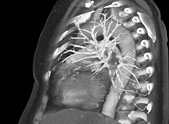

CT des Herzes (Cardio-CT)

• Herz

Kardio-CT ist ein spezielles Röntgen-Schnittbildverfahren zur Untersuchung und sehr exakten Lokalisierung von aterosklerotischen Veränderungen an Herz und Gefäßen.

Computertomographische Untersuchungen am Herzen erfordern aufgrund der schnellen Bewegungen und der z.T. kleinräumigen Strukturen besondere Technologien. Mit der Einführung der modernen Mehrschicht Spiral-CT (MSCT) lassen sich erstmals Herz und Herzkranzgefäße mit sehr dünnen Schichten darstellen.

Durch intravenöse Kontrastmittelgabe und Synchronisierung der MSCT-Daten mit dem gleichzeitig aufgenommenen EKG des Patienten gelingt es in der CT-Koronarangiographie, den gesamten Koronarbaum einschließlich koronarer Bypässe detailreich darzustellen.